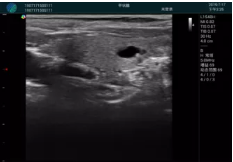

可視化甲狀腺穿刺引導

甲狀腺囊性結(jié)節(jié),囊壁鈣化,透聲好

甲狀腺囊性占位